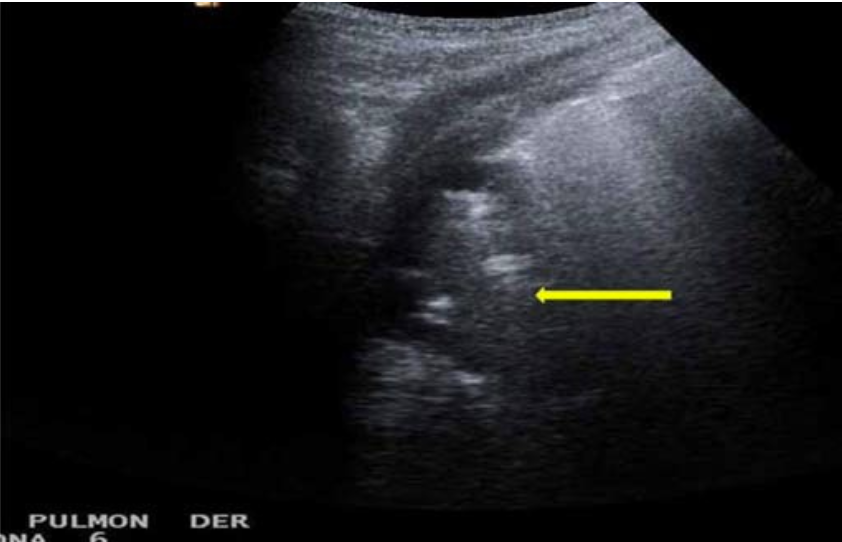

胸膜线

位于 2 根相邻肋骨之后的 5 mm 位置,厚约 2 mm,正常情况下可随呼吸运动而上下活动(胸膜滑动征)。

A 线

为水平伪像,指平行于胸膜线的多个短线状强回声,是声波在胸膜处发生的混响效应,其间距相等